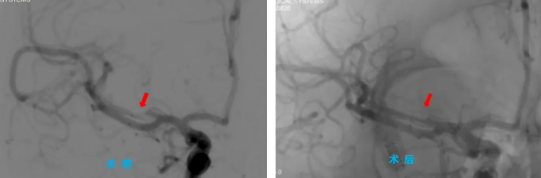

手術(shù)當(dāng)天,院長助理、神經(jīng)內(nèi)科主任程偉與神經(jīng)內(nèi)科三病區(qū)副主任彭偉聯(lián)手為患者主刀,通過高難度的微創(chuàng)介入治療,成功為患者大腦中堵塞的血管進(jìn)行了球囊擴(kuò)張并置入支架,打通了“生命通道”。術(shù)后,患者手腳能活動了,說話也清楚了,恢復(fù)得一天比一天好,一周后,患者康復(fù)出院。